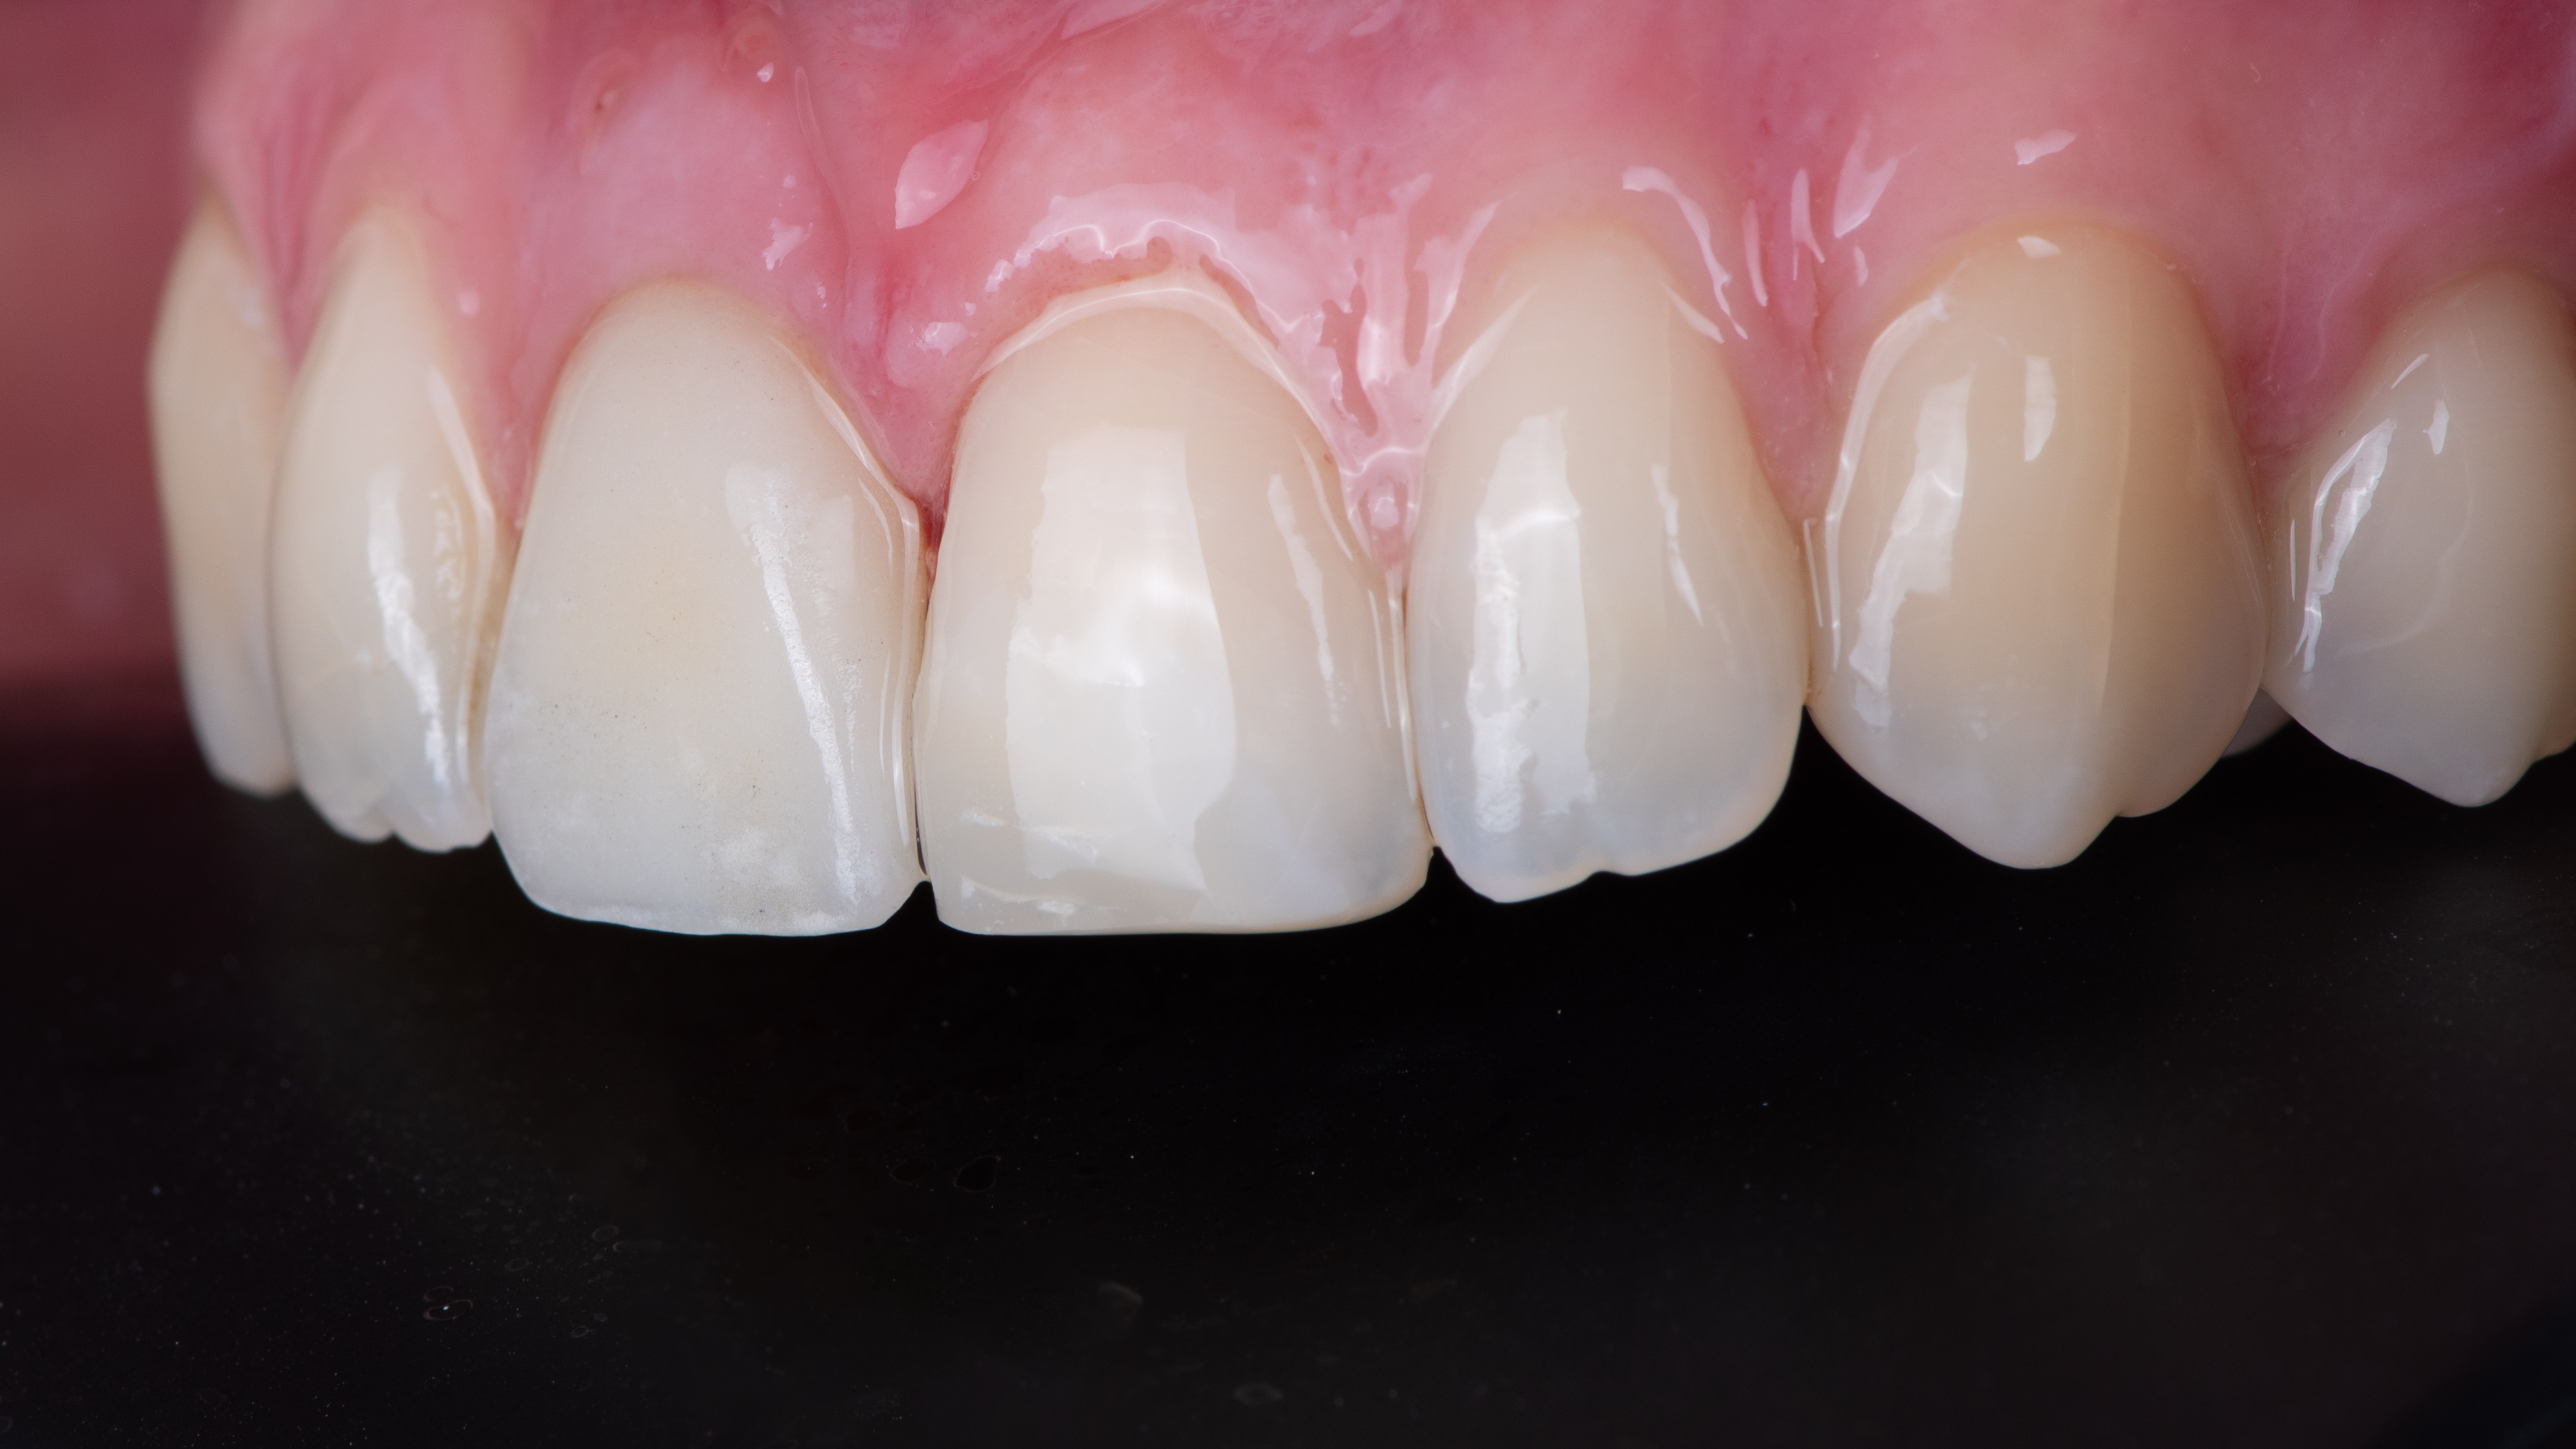

La patiente revient pour la pose de la prothèse d’usage. Nous réalisons donc un essayage de cette prothèse d’usage avant de réaliser le composite sur la dent 21.

Nous constatons que la cicatrisation est alors optimale et que la prothèse d’usage s’intègre parfaitement à son environnement (Photo 20).